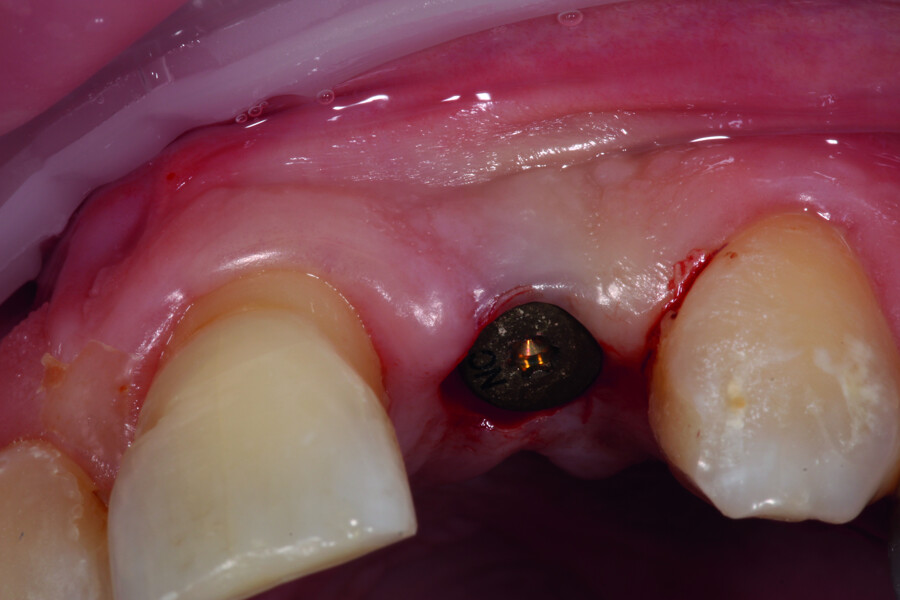

Digitising your implant practice